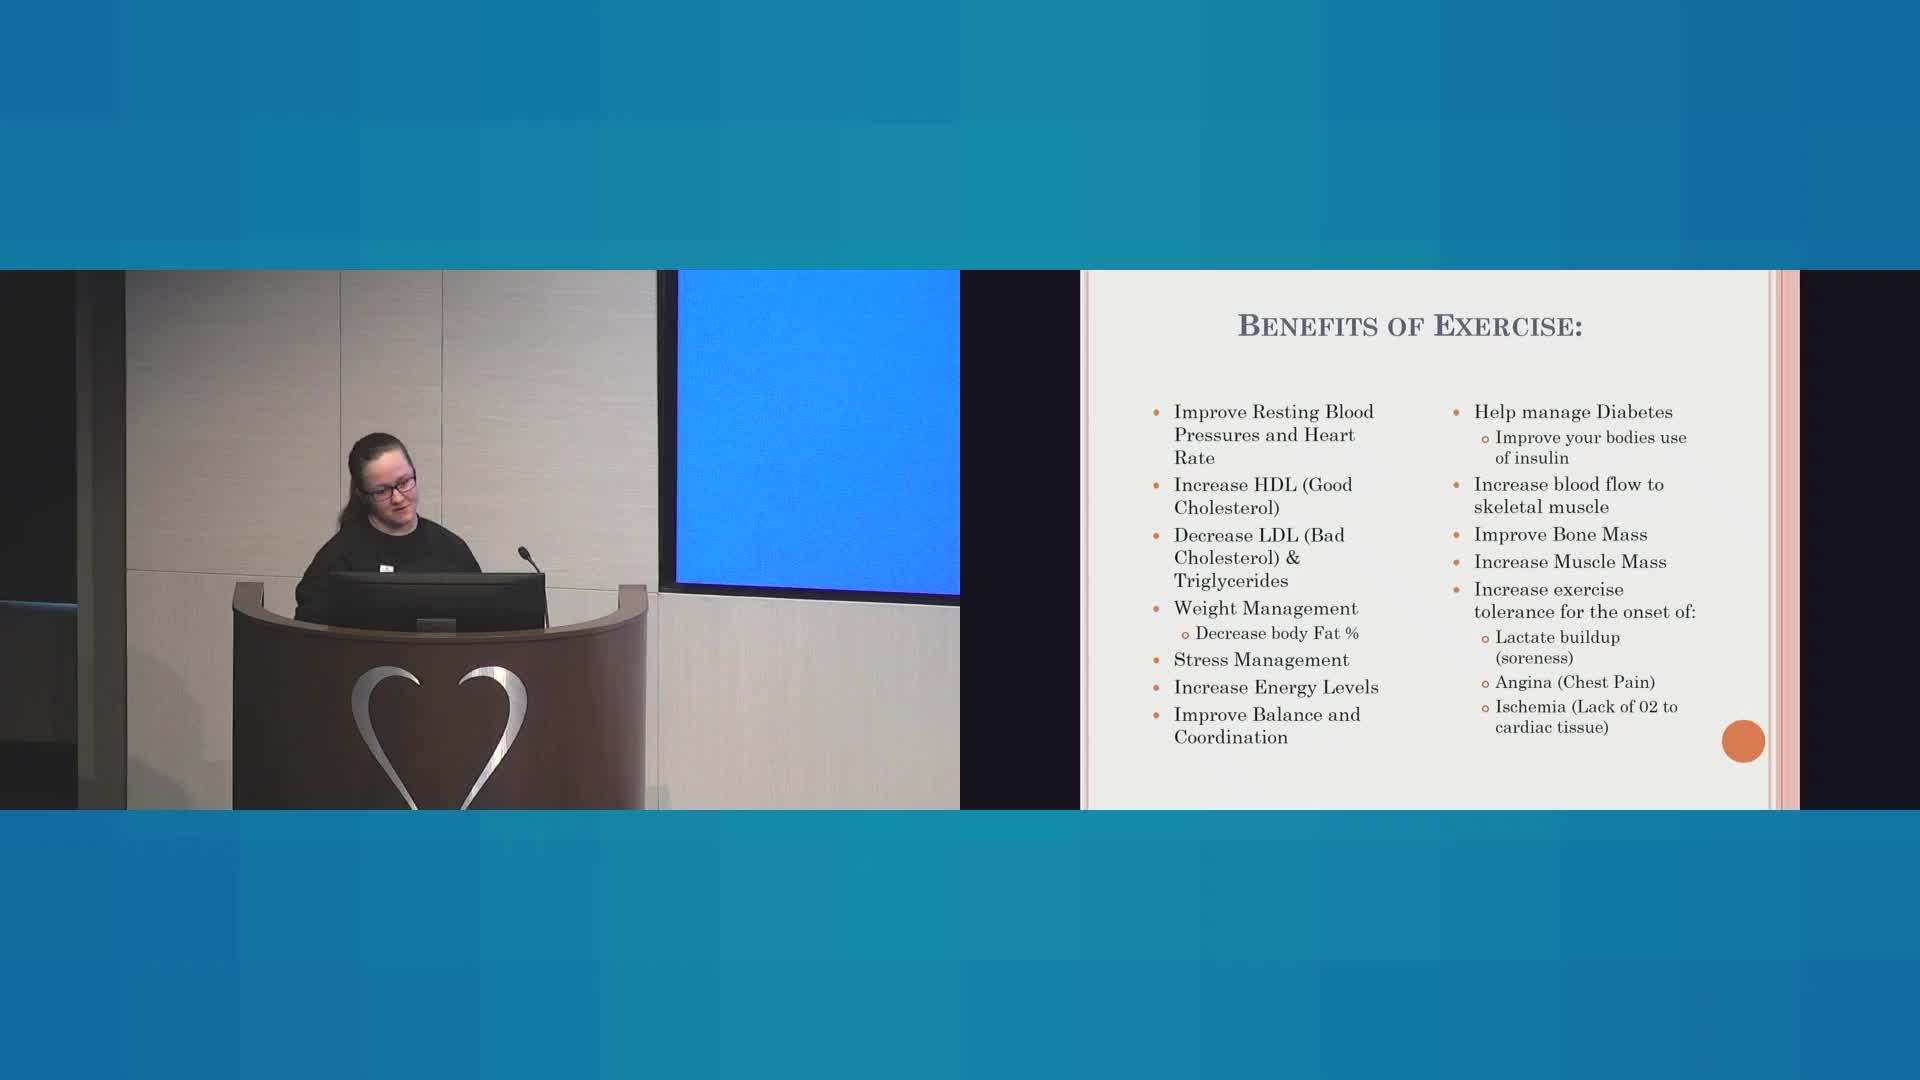

Our mission is to provide a collaborative environment and educational opportunities for physicians, scientists, nurses, and medical professionals to discuss and teach advanced techniques, improve clinical knowledge, and enhance the ability to provide excellent patient care, which ultimately improves patient health outcomes. To that end, the education program has strived to meet this goal educating and training the local, regional, and national medical community on the most recent advancements in medical science and research.